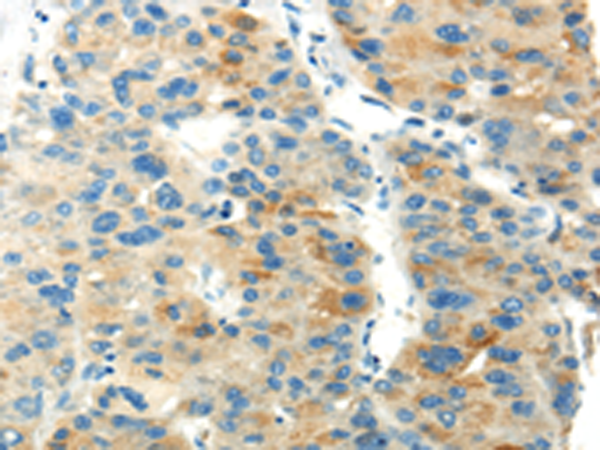

分类: 科研抗体货号: P12418别名: T1A; GP36; GP40; Gp38; OTS8; T1A2; TI1A; T1A-2; AGGRUS; HT1A-1; PA2.26应用: WB,IHC反应种属: Human